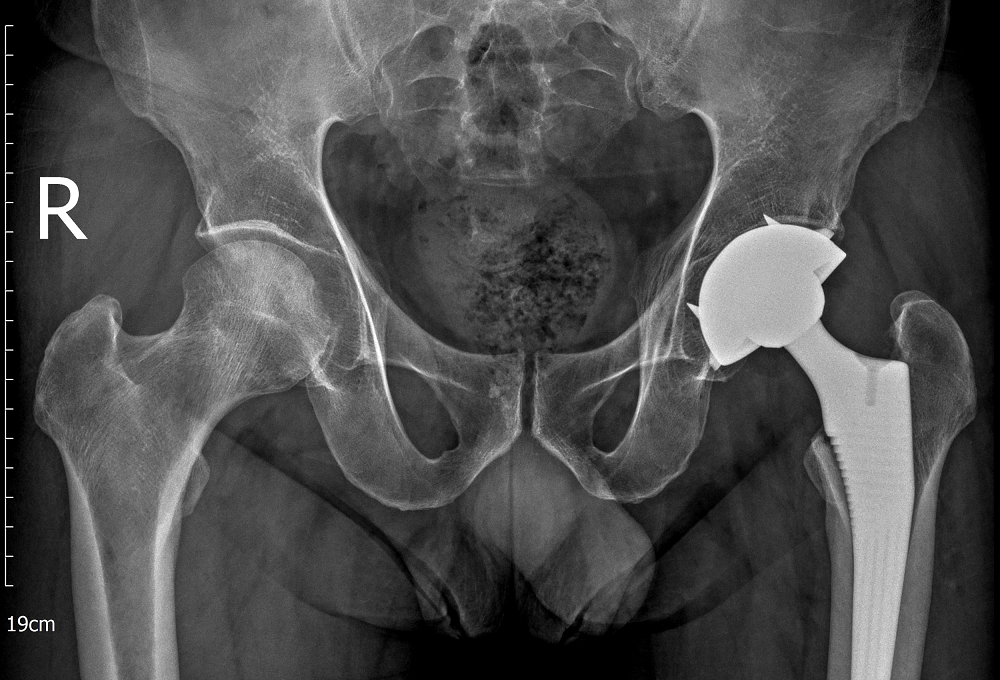

Bệnh nhân nghiện thuốc lá bàng hoàng khi bác sĩ thông báo bị… hoại tử xương- Ảnh 2.

Bệnh nhân được bác sĩ thực hiện thành công cuộc phẫu thuật thay khớp háng toàn phần bên trái

Với trường hợp này, khớp háng trái đã tiến triển đến giai đoạn nặng, không còn khả năng bảo tồn, các bác sĩ buộc phải chỉ định thay khớp háng toàn phần nhằm giảm đau, phục hồi chức năng vận động và tránh nguy cơ tàn phế cho người bệnh. Trong khi đó, khớp háng bên phải vẫn còn khả năng bảo tồn nên các bác sĩ lựa chọn phương pháp phẫu thuật giảm áp cổ xương đùi để cải thiện tuần hoàn, làm chậm quá trình hư khớp.